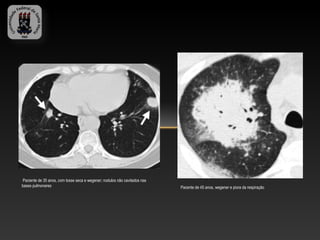

Paciente de 35 anos, com tosse seca e wegener; nodulos não cavitados nas

bases pulmonares                                                            Pacente de 45 anos, wegener e piora da respiração